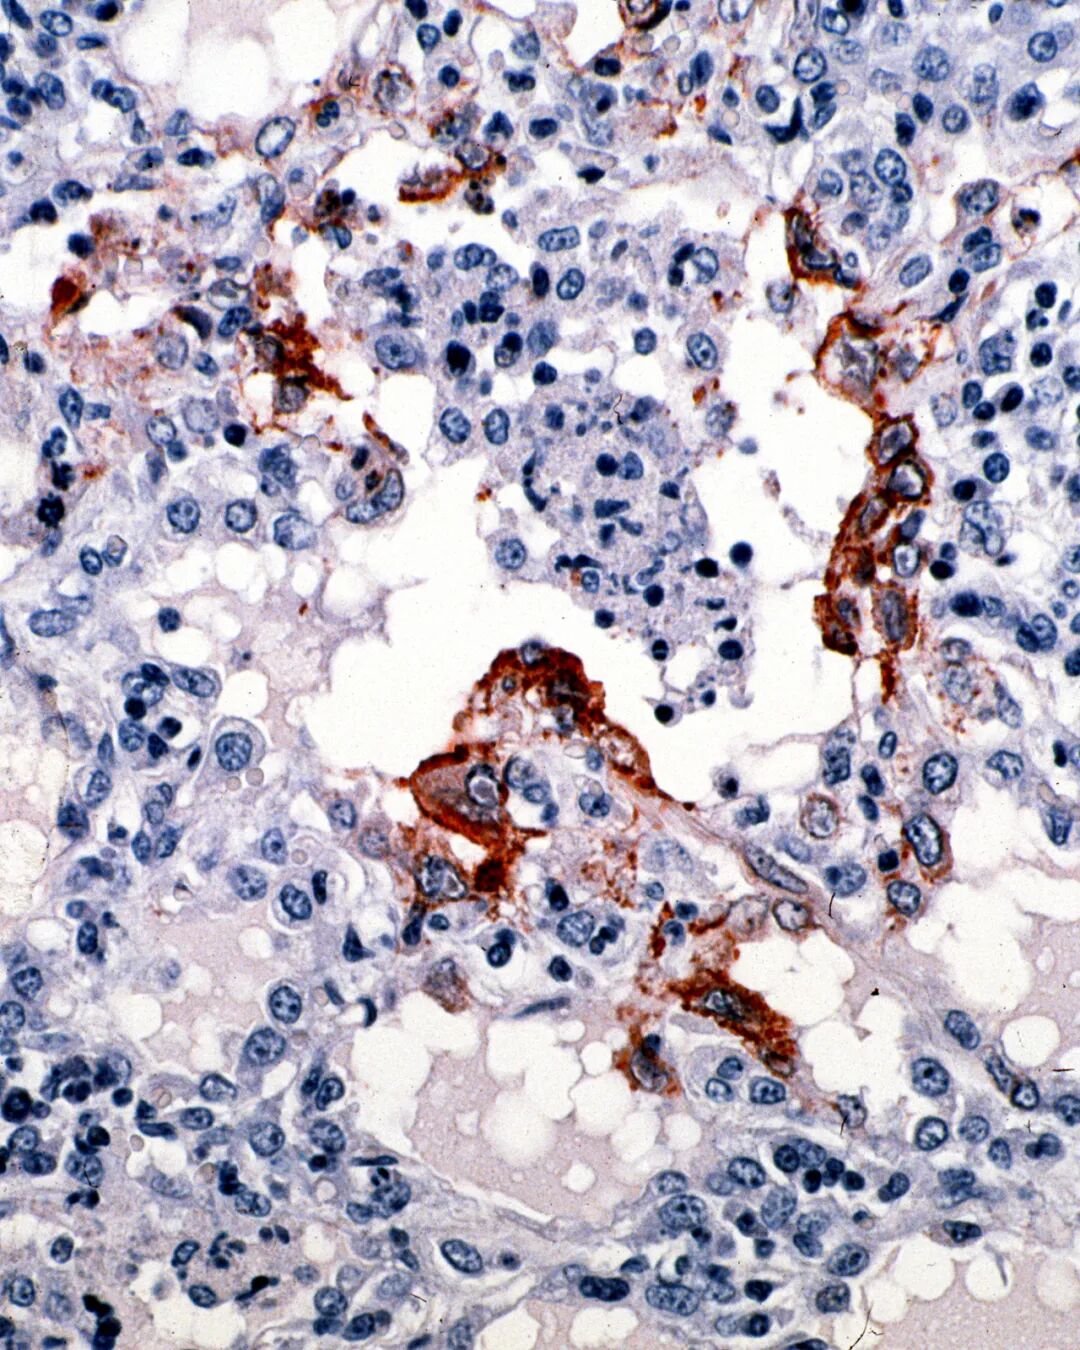

棕色部分即为侵扰肺部的尼帕病毒,这种感染势必会对呼吸系统造成影响。(图/Wikimedia Commons)